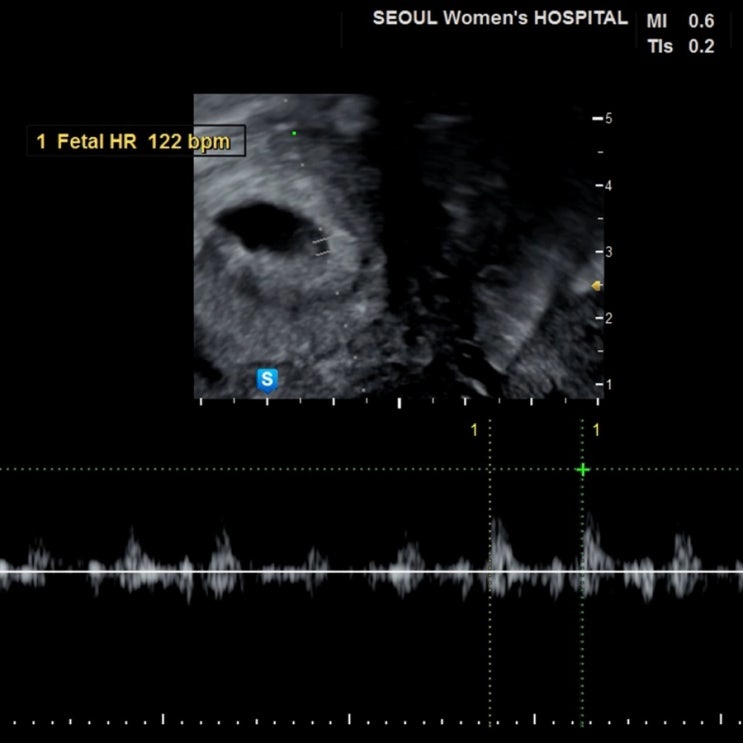

[임신 4주, 5주, 6주] 임신 극초기 증상, 초음파, 심장박동수, 아기크기

2024년 3월 16일 처음으로 아기집 본 날 초음파 보기 전 까지 얼마나 떨리고 긴장됐는지 근데 내 몸이 느껴...